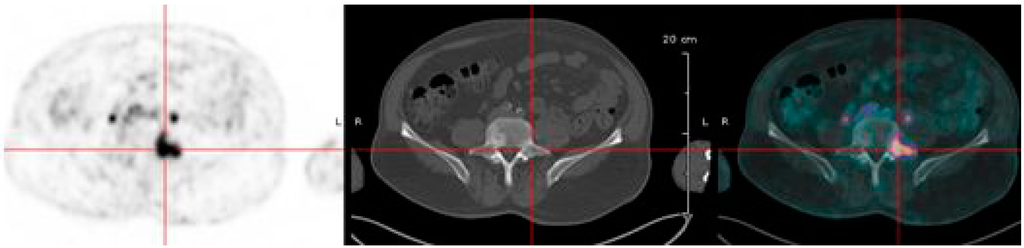

6.2. 68Ga-Peptide for Pretargeted Immuno-PET in CEA Positive Tumors